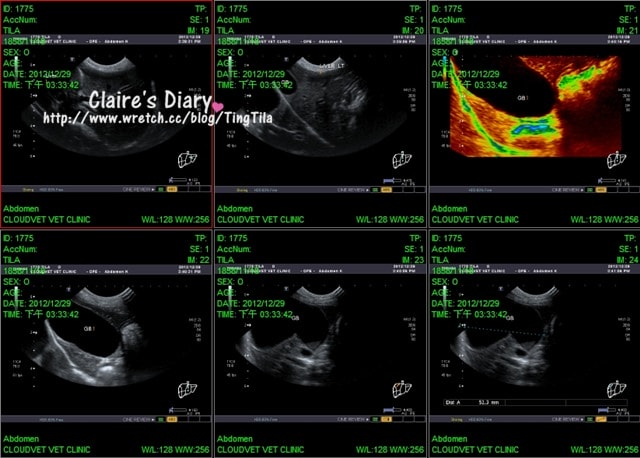

當照到膽的時候,蔡醫生突然蹦出一句話

「大膽的傢伙~」

我還以為是TILA亂動所以蔡醫生說她大膽,結果….是TILA的膽真的很大

蔡醫生說膽很大的case,偶爾會出現容易嘔吐的情形.吐胃酸之類的

而通常膽大沒有什麼不好,只要沒有阻塞沒有結石都沒有問題!

肝膽指數都OK,在超音波下的檢查也OK!

腎指數(BUN)看起來是有比較高,但是在超因波的檢查下,腎很好~所以不用擔心

整體器官都很正常,就連很大的膽也長的非常漂亮!!

蔡醫生很喜歡用漂亮這字^^